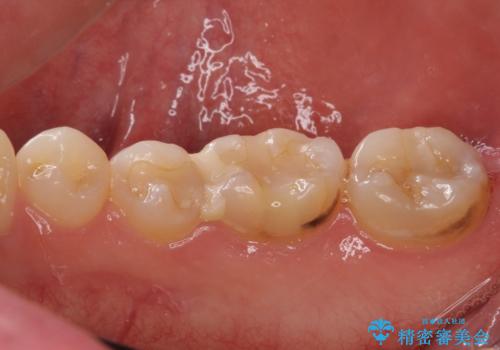

当初はセラミックインレーによる修復治療を希望されいましたが、カウンセリングの結果、審美性よりも安定性を優先され、PGAインレー(ゴールドインレー・白金加金合金インレー)による治療を行うこととしました。

ゴールドインレーをご自身で選択いただいたものの、どういった仕上がりとなるか不安を感じていたようですが、実際に装着された口腔内をご覧になり、思ったほど金属色が気にならないとのことでした。

咬んだ感触はご自分の歯のときと比べ全く遜色なく、患者様には大変満足していただきました。